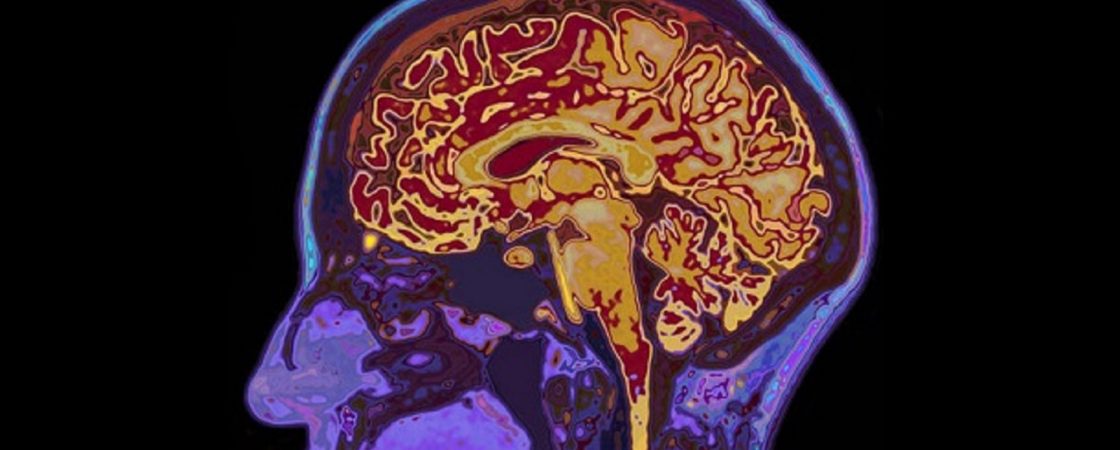

Multiple Sklerose und Borreliose: Werden hier Krankheiten verwechselt?

Die Sache mit der MS, beziehungsweise deren schulmedizinischer Therapie sehe ich sowieso sehr kritisch. Dies hatte ich bereits in meinem Grundsatzbeitrag zur Multiple Sklerose dargelegt. Gleiches gilt übrigens auch für die Borreliose: Borreliose – Alternative Therapie und Behandlung. In diesem Beitrag erwähne ich Dr. Klinghardt, der ebenfalls einen Zusammenhang zwischen Borreliose und Multipler Sklerose gesehen hat. Und falls …